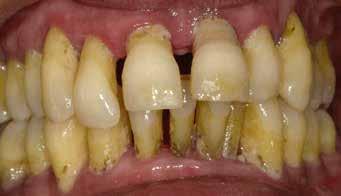

Klinikánkon egy teljesen fogatlan, hagyományos akrilát fogpótlással helyreállított 65 éves férfi beteg jelentkezett, aki nem kielégítő alsó fogsorretencióra és az azzal járó problémákra panaszkodott, beleértve a kifejezetten az alsó fogsorához kapcsolódó gyenge beszéd és rágásfunkciót. A klinikai vizsgálat gömbölyűtől a késhegyig terjedő mandibulagerinc formát és megfelelő vertikális, de nem megfelelő vízszintes csontmennyiséget állapított meg, különösen a hátsó területen (1. ábra) 10

A diagnosztikai panoráma röntgenfelvételen a mandibula íve mérsékelt IIIIV. osztályú atrófiával és megfelelő térfogatú, viszonylag sűrű III. típusú kortikális csonttal jelentkezett az interforaminális területen (2. ábra).